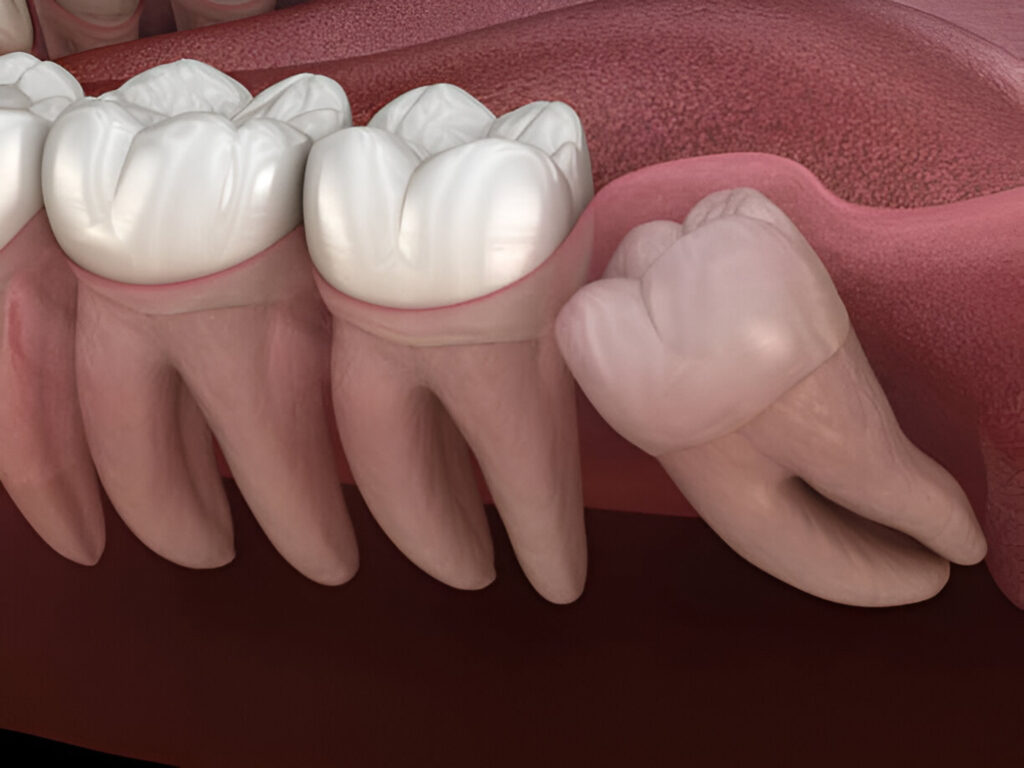

Wisdom Teeth Removal

Wisdom teeth or third molars classically appear in the late teens or early twenties age group. In several cases, they develop crowding, misalignment, or painful infections which necessitates the removal of the teeth to maintain the overall health of an individual's mouth.

What are Wisdom Teeth

Wisdom teeth removal is a common dental procedure to extract the third molars—typically the last teeth to erupt, usually between the ages of 17 and 25. Often, these teeth do not have enough room to grow properly, leading to pain, crowding, or infection. In such cases, removal is recommended to protect the health of your gums, teeth, and jaw.